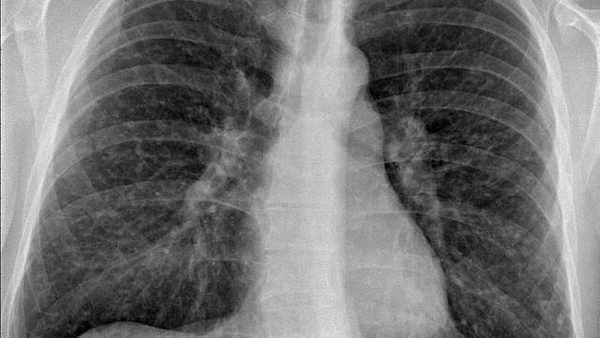

Белые пятна на рентгеновском снимке — гранулемы. Источник: Mikael Häggström / Wikipedia (CC0)

При подозрении на саркоидоз проводятся как инструментальные, так и лабораторные исследования. Прежде всего это рентгенография легких, по которой определяют стадию заболевания. Для уточнения структуры легких и обнаружения других патологических изменений также проводится компьютерная и магнитно-резонансная томографии.

На основании рентгенологической картины легких выделяют 5 стадий заболевания: